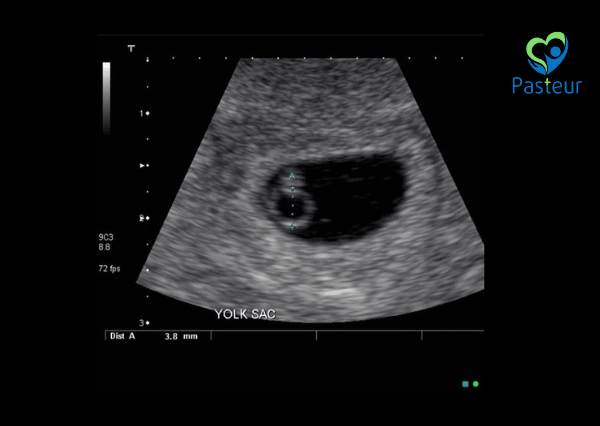

Khi siêu âm thai từ khoảng tuần thứ 5 – 6, bác sĩ có thể thấy yolksac bên trong túi thai nếu thai đã vào tử cung đúng vị trí. Việc phát hiện yolksac là một tín hiệu tốt, chứng minh rằng thai đang phát triển theo đúng lộ trình tự nhiên.

4. Kích thước yolksac bao nhiêu là bình thường?

Một yolksac bình thường sẽ có đường kính vào khoảng < 5 mm. Tuy nhiên, nếu kích thước yolksac vượt quá ngưỡng này, có thể cần theo dõi thêm vì:

Kích thước > 5.6 mm: có thể liên quan đến nguy cơ sảy thai sớm hoặc thai ngừng phát triển.

Kích thước không đều, hình thái bất thường (dẹt, méo, không tròn đều): có thể là dấu hiệu cảnh báo bất thường nhiễm sắc thể.